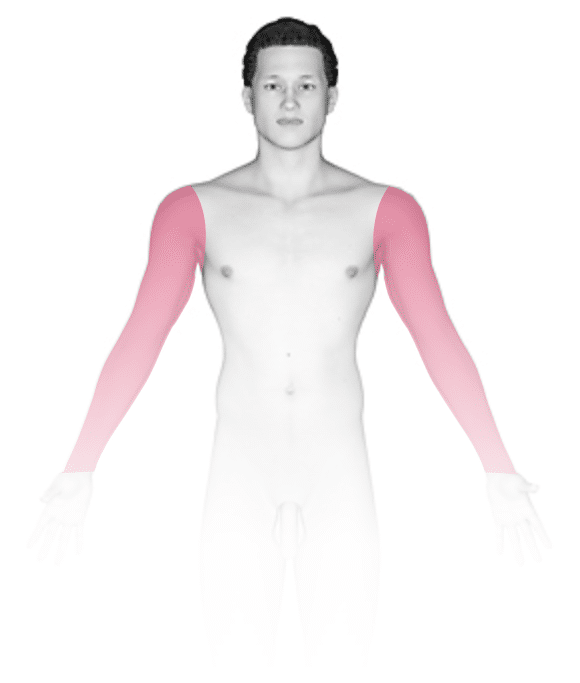

Less commonly, erythrasma can be found in the buttock crevice or in the folds underneath the breasts. In certain individuals, especially in those with diabetes, the infection can become widespread and can involve the trunk, arms, and legs.